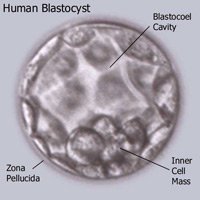

Blastocyst Culture and Transfer

| Blastocyst culture and transfer is a newer technique which increases implantation and pregnancy rates as it allows the embryo to grow to a more matured stage in laboratory under controlled environment. Mature embryos have a higher chance of implantation and consecutive pregnancy. |

During the cleavage of the early foetus, zona pellucida hardens. This development is normal and the purpose is to keep the cells in the egg together. Removing the egg for in vitro fertilization and micro insemination takes it out of its natural environment. This procedure tends to lead to egg shells that harden faster those of normally fertilized eggs.

Especially women older than 37 years of age, have a tendency to produce eggs with a harder zona pellucida than younger women. The same goes for women with a high level of follicle stimulating hormone (FSH). This can be diagnosed from a blood sample. Especially women older than 37 years of age, have a tendency to produce eggs with a harder zona pellucida than younger women. The same goes for women with a high level of follicle stimulating hormone (FSH). This can be diagnosed from a blood sample.

The problem of a harder zona pellucida is that the egg may not hatch and thus not attach to the woman’s womb. Hatching of the egg is necessary to become pregnant. We know that eggs from older women have problems hatching, explaining why some older women have problems becoming pregnant.

Laser assisted hatching is one out of several methods to help the fertilized egg hatch and attach to the womb. Other methods are acid or mechanical hatching of one a part of zona pellucida. Laser assisted hatching is a gentle and safe way to weaken a part of zona pellucida. After treating the fertilized egg with laser assisted hatching, we transfer the embryo into the woman’s womb. In most cases the embryo will attach for normal growth and development.